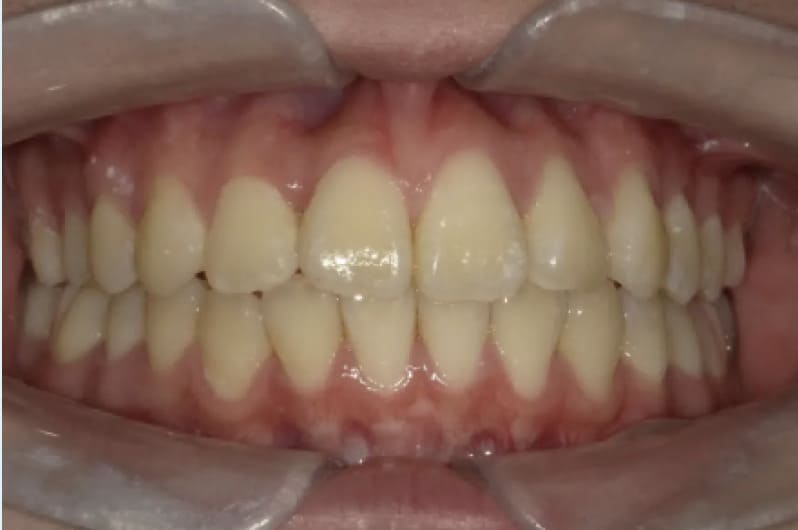

| After | ![]() |

| 性別 | 男性 |

| 年齢 | 小学校高学年 |

| 治療費用 | 902,000円 |

| 治療期間 | 1年9か月 |

| 治療内容 | マウスピース矯正 |

| リスク 副作用 |

矯正治療の一般的なリスクといたしましては、治療中のお痛み・歯根吸収・歯肉退縮・治療後の後戻りなどが生じる可能性があります。矯正治療は始めると、元の状態に戻すのが難しいことがあります。 |